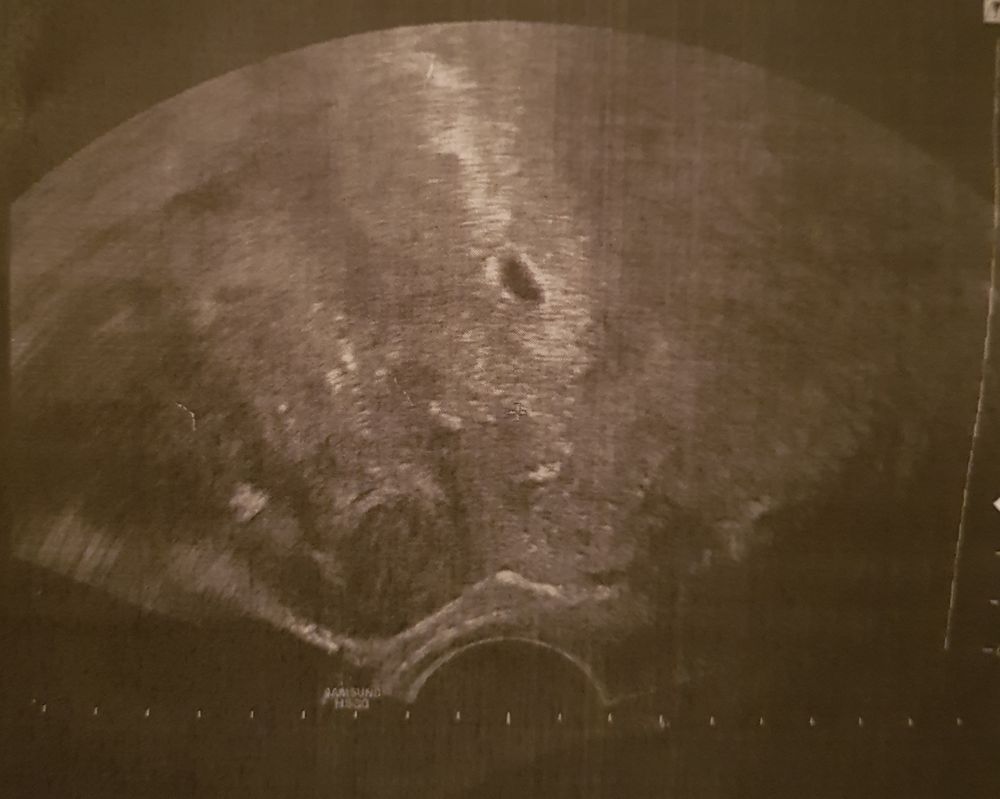

Юлия , спасибо) на 13 дпп хгч был 145. Узи сделали на 19 дпп